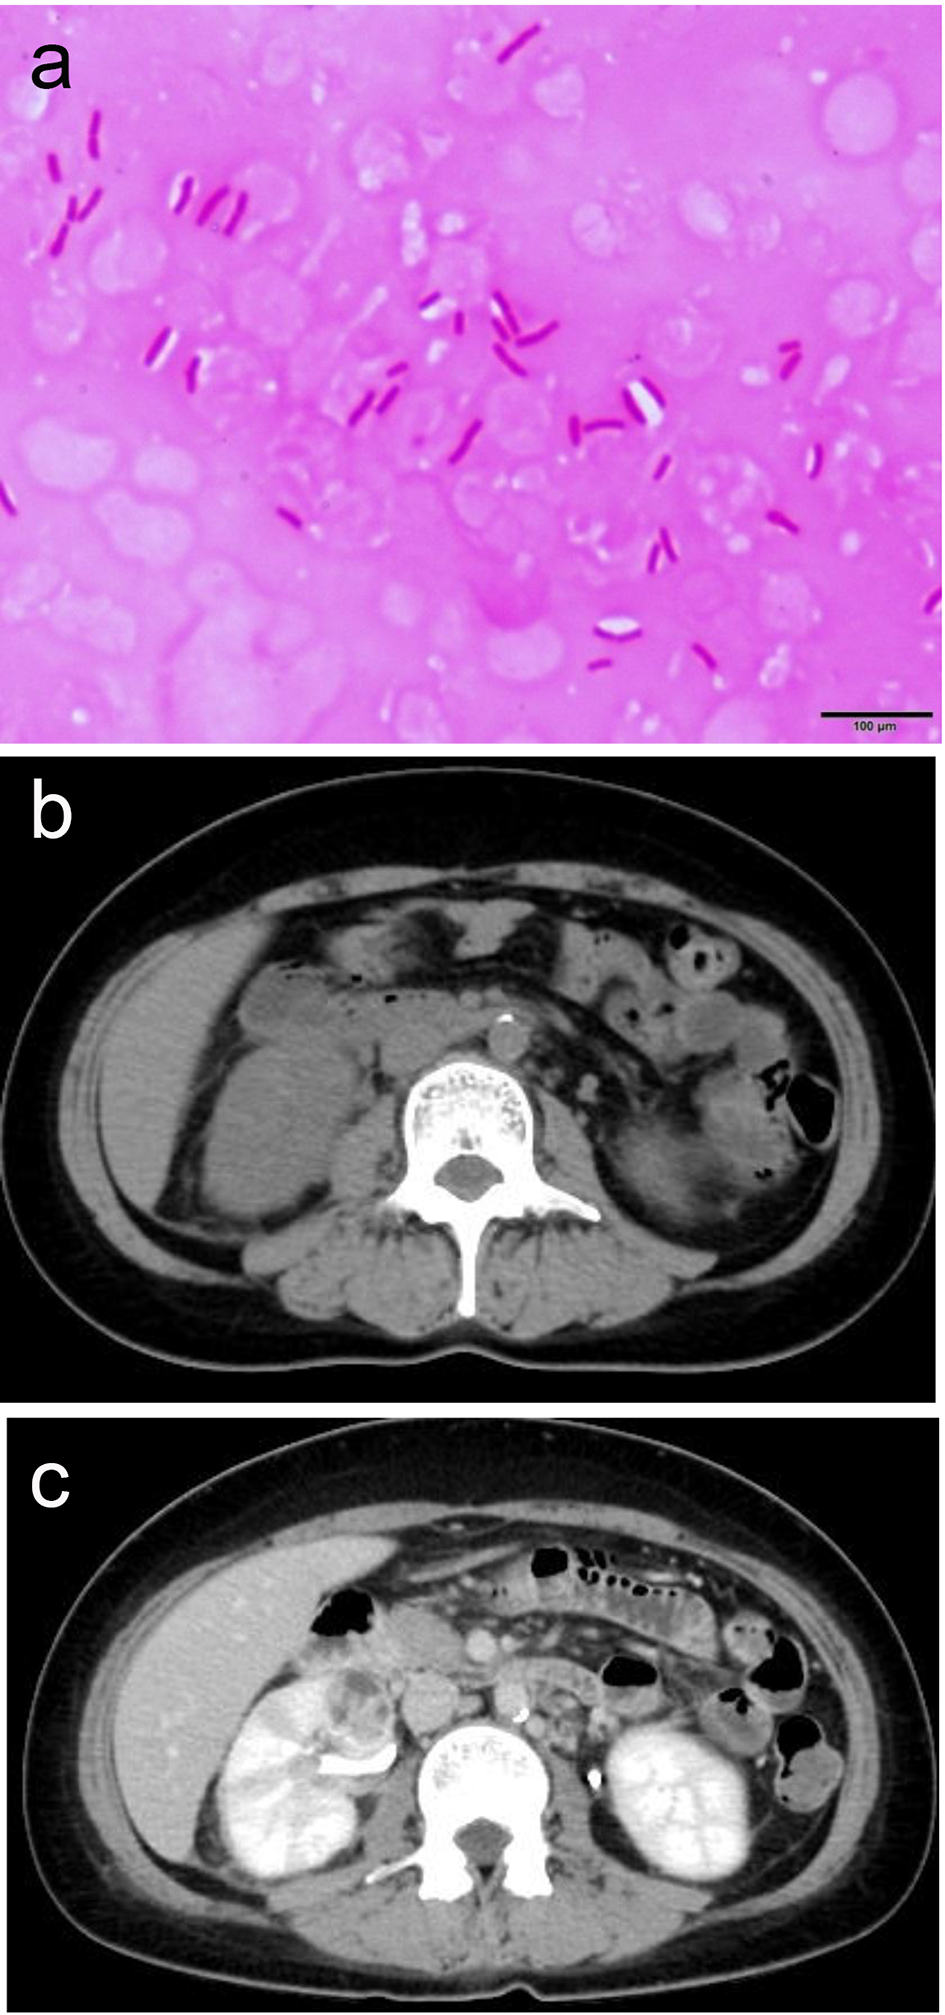

A 41-year-old female visited a home clinic complaining of high grade fever (38.5 °C) and a severe headache which lasted for a couple of days. Meningitis was suspected from her medical consultation and physical examination. Following that, she was referred to our emergency department for further examination. Her past medical history included diabetes milieus type II, which was treated using oral drugs. Physical examination upon arrival revealed that her blood pressure was 140/80 mm Hg, heart rate was 86 beats/min with regular rhythm, blood oxygen saturation was 100% under atmospheric conditions, and body temperature was 36.0 °C. Blood chemistry analyses revealed severe inflammation (12,900/μL white blood cells (WBCs)/μL with 83.3% neutrophils and 39.2 mg/dL C-reactive protein), mild hyponatremia (131 mEq/mL), coagulant dysfunction (103% prothrombin, 39.0 s activated partial thromboplastic time, 1,014 mg/dL fibrinogen, and 3.7 μg/mL D-dimer), and impaired glucose tolerance (231 mg/dL glucose and 8.0% hemoglobin A1c). Further, mildly decreased albumin (3.7 g/dL), and mildly increased total bilirubin (1.7 mg/dL), gamma-glutamyltransferase (211 IU/L), alkaline phosphatase (469 IU/L), and lactate dehydrogenase (355 IU/L) were also revealed. Although she suffered intolerable head pain with queasiness, physical examination revealed no neck stiffness, Kernig, or Brudzinski sign, or costovertebral angle tenderness. Electrocardiography revealed a normal, regular heart rhythm without ST changes. Brain and chest CT revealed nothing that suggested infected lesions. Cerebrospinal fluid (CSF) culture and urine culture detected no bacteria, but blood culture revealed the presence of Escherichia coli (Fig. 1a). Urinalysis revealed 1 - 4 WBCs per high-power field (HPF) and 5 - 9 red blood cells (RBCs)/HPF with no bacteria. Non-contrast CT revealed mildly swollen right kidney accompanied by fat stranding in the peritoneal cavity, which suggested inflammation (Fig. 1b). Then contrast-enhanced CT was performed on the day of admission, revealing wedge-shaped, non-contrast, and low density mass-like lesions in the right kidney consistent with AFBN (Fig. 1c). Consequently, anti-bacterial agents were initiated (Fig. 2). After 3 weeks of antibacterial treatment, chemical analyses of inflammatory response dramatically improved, and symptoms completely disappeared.

![]() Click for large image | Figure 1. (a) E. coli was revealed by blood culture. (b) Mildly swollen right kidney accompanied by fat stranding in the peritoneal cavity suggesting inflammation. (c) Wedge-shaped, non-contrast, and low density mass-like lesions in the right kidney consistent with AFBN. |